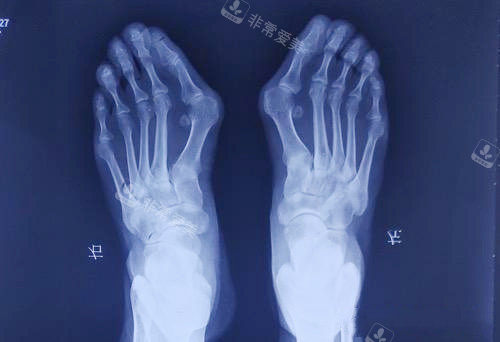

大脚骨X光片图片

首先是“更准一些检查”,除了常规的足部X光片,还会用3D足部扫描、压力测试等设备,详细评估拇外翻的角度、足弓形态、受力分布,甚至分析走路时的步态,找出问题根源;

大脚骨拍片